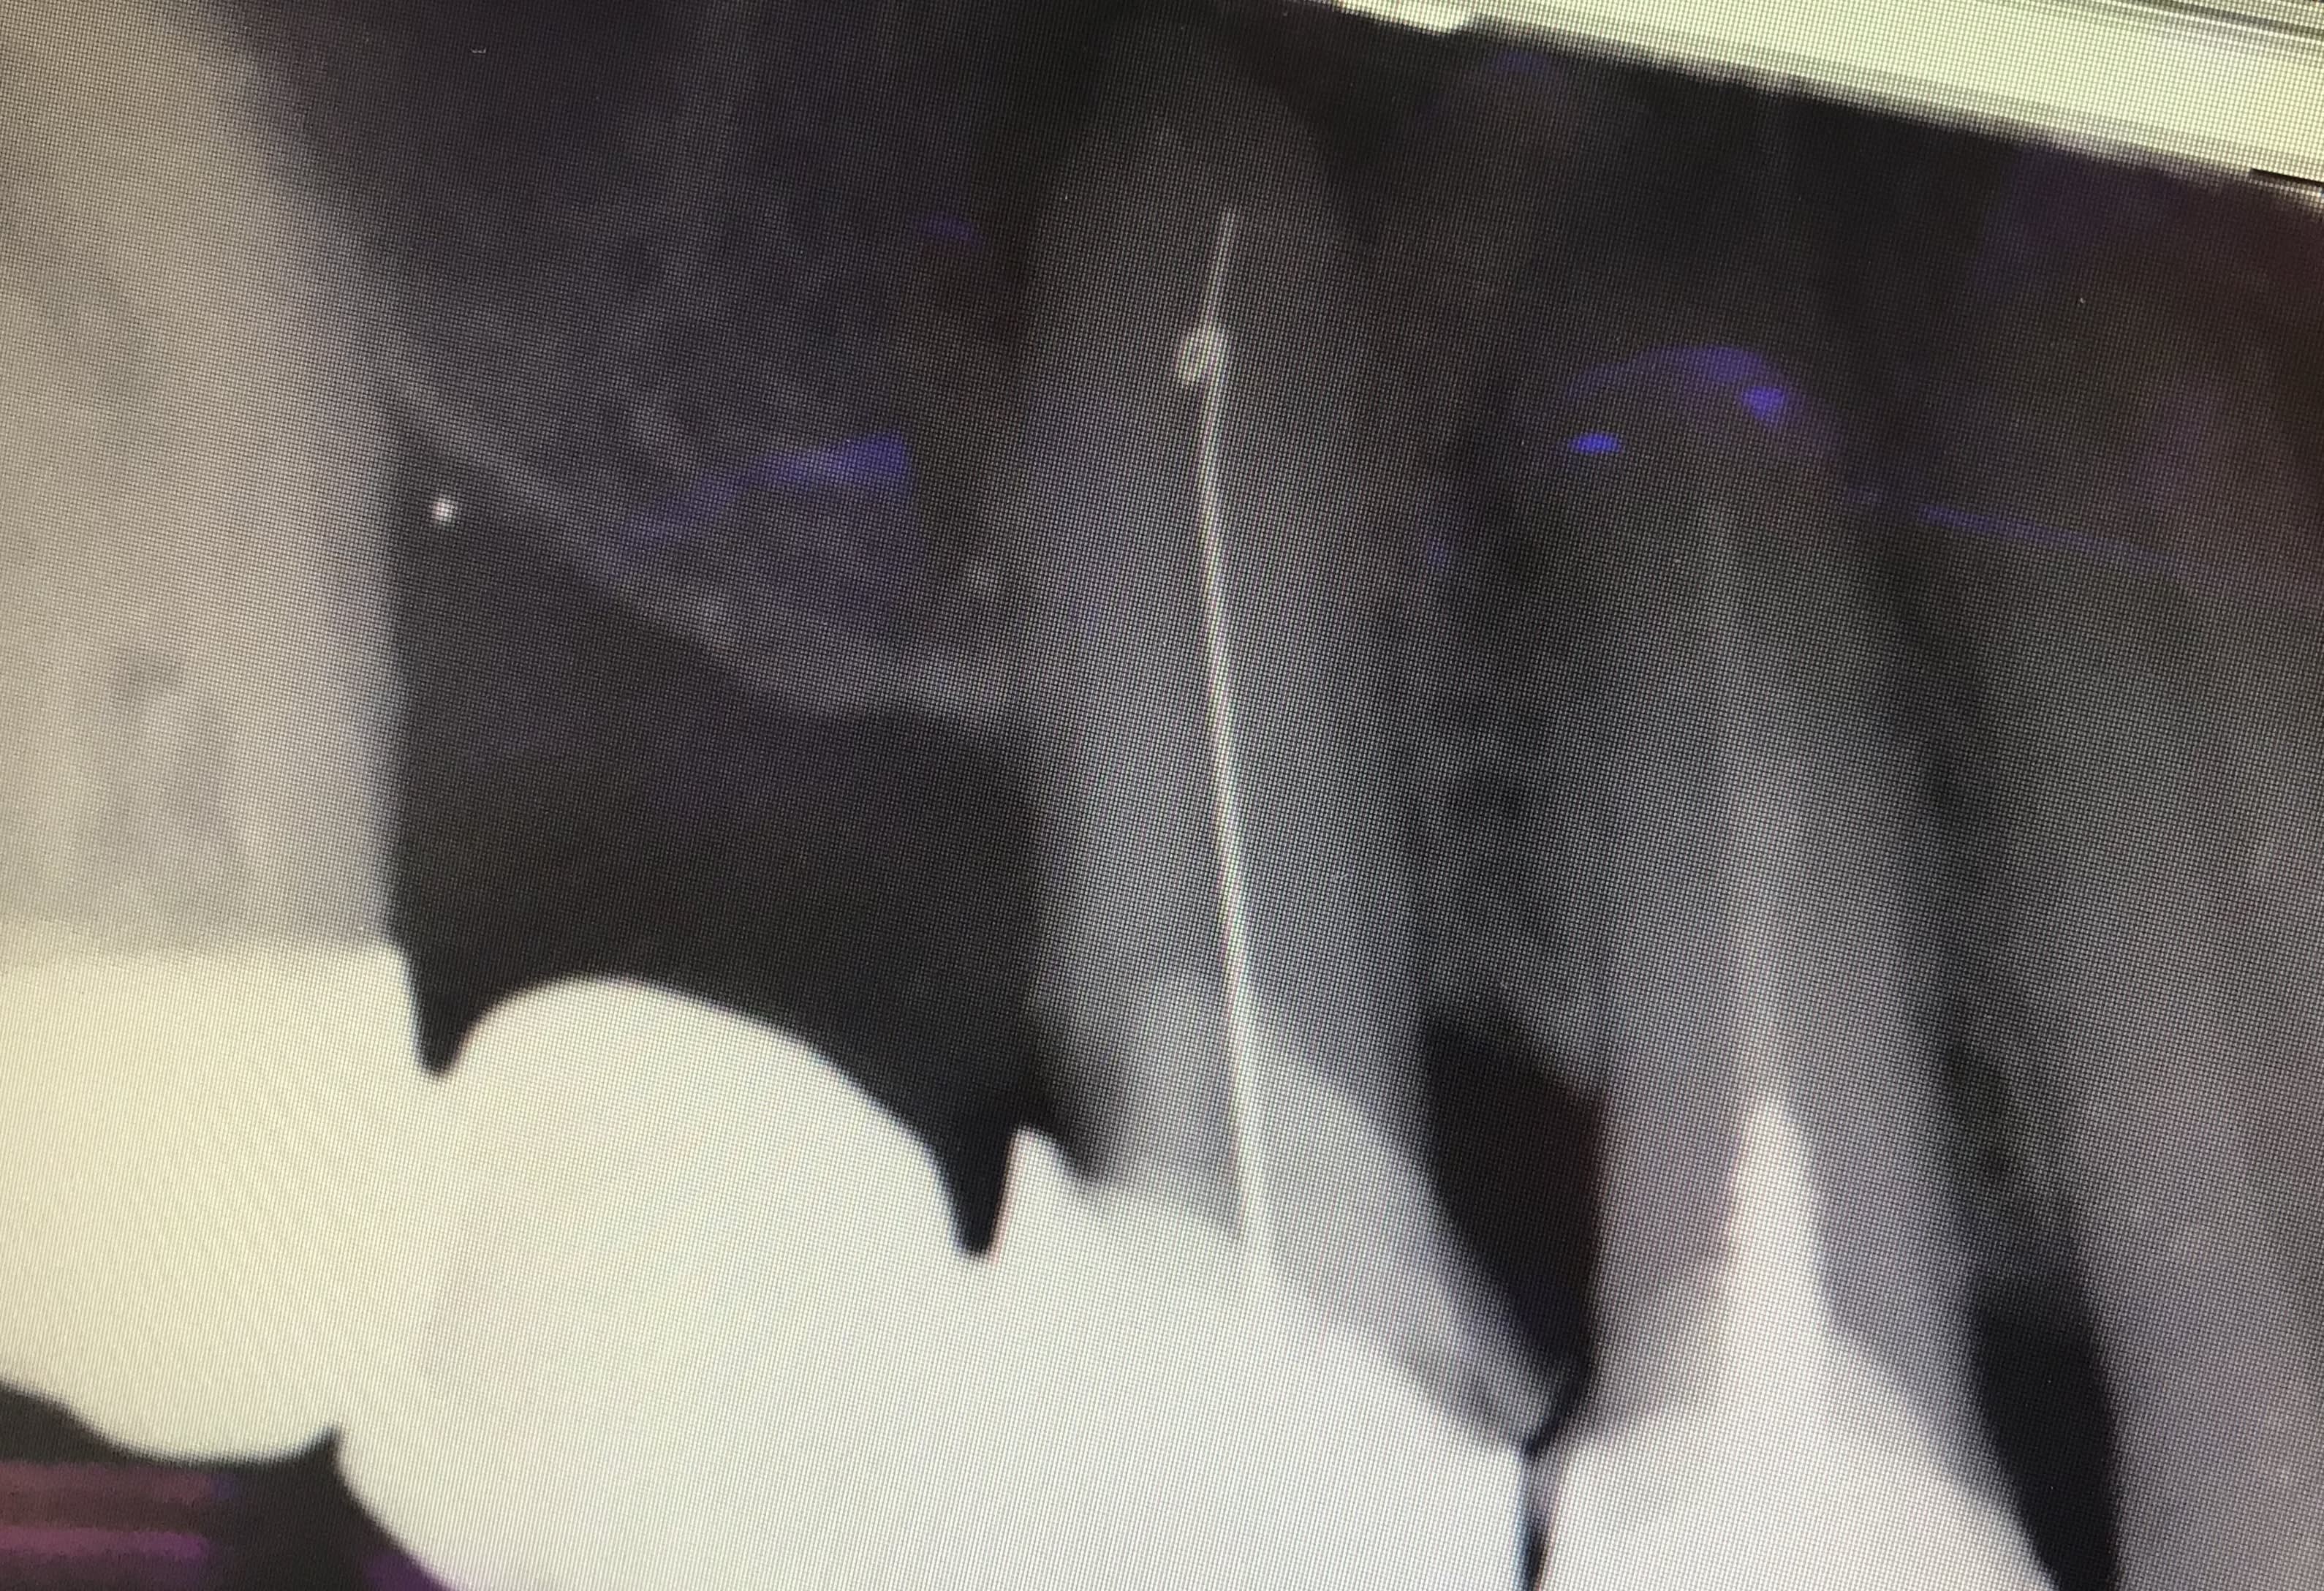

Est-ce que les dents avec des obturations à l’ancienne ça se retraite bien ? Ils ont fait un noeuds à l’apex

Sinon autrement ERI :))